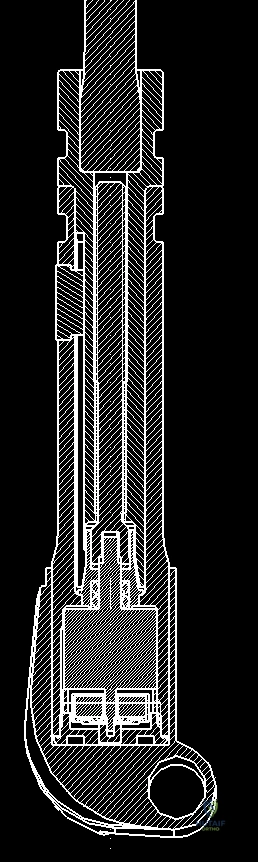

The deployment of an expandable endoprosthesis is not merely a geometric exercise in matching bone length; it is a complex biomechanical intervention. The growing skeleton is highly responsive to mechanical loading, governed by Wolff's Law. When a massive metallic implant is introduced, it alters the physiological stress distribution, leading to potential stress shielding, osteolysis, and implant loosening over time. Expandable prostheses must be engineered to mitigate these forces while housing an internal lengthening mechanism—whether mechanical (e.g., minimally invasive worm-drive) or non-invasive (e.g., electromagnetic induction). Furthermore, the fixation of these devices in the pediatric intramedullary canal, which is often narrow and structurally immature, requires specialized techniques, including the use of custom-fluted stems, hydroxyapatite-coated collars for extracortical bone bridging, and precise cementing techniques to ensure long-term survivorship of the construct.

Once the resection level is determined, accurate measured radiographs and MRI cross-sections are transmitted to the prosthesis engineers. They will custom-fabricate or modularly assemble the implant to match the resected bone length precisely, accounting for the required joint line restoration and soft tissue tension. We currently utilize two main categories of expandable prostheses: minimally invasive (mechanical) and non-invasive (electromagnetic).

The Minimally Invasive Expandable Prosthesis (e.g., the JTS implant) is lengthened via an internal worm-drive mechanism. It requires a minor percutaneous procedure where an Allen key is inserted through a small stab incision to manually turn the mechanism. While highly reliable and mechanically robust, it carries a cumulative risk of infection with each lengthening procedure. Conversely, Non-invasive Expandable Prostheses (e.g., Repiphysis or Mutars Xpand) utilize an internal electromagnetic motor driven by an external magnetic coil placed over the limb in the outpatient clinic. This eliminates the need for repeated anesthesia and surgical incisions, drastically reducing the risk of secondary periprosthetic joint infection, though these devices are mechanically more complex and historically prone to internal mechanism failures.